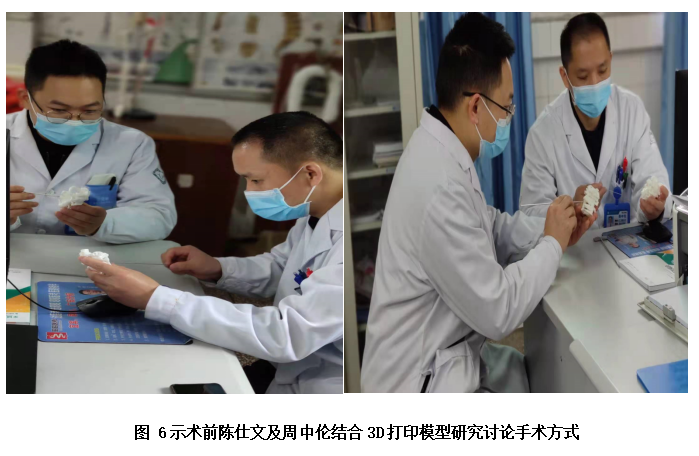

面对患者和家属的信任、期待,岳池中医院骨伤科脊柱团队也高度重视该手术。为了减轻患者痛苦及预防相关并发症,促进患者快速康复,经骨伤科全科讨论,决定由脊柱专业组周中伦副主任医师及陈仕文主治医师共同主刀为患者进行手术治疗。在完善相关术前检查排除手术禁忌的条件下,该团队为患者精心设计了手术方案。且为进一降低手术风险,陈医师发挥自已的专业特长,为患者进行了上颈椎的3D模型重建及钉道设计;考虑到枢椎的椎动脉高跨情况,特别为患者设计并制作了枢椎的3D打印导板以引导植入螺钉。

当充分完成术前准备后,于上月下旬,在麻醉科、手术室等医务人员的密切配合下,周医师及陈医师上台为杨阿姨实施了该手术。经过精心操作和不懈努力,成功为患者行了3D打印导板引导下的颈椎后路寰枢椎椎弓根螺钉内固定及取髂骨寰枢植骨融合术,术中患者出血少,手术取得圆满成功。